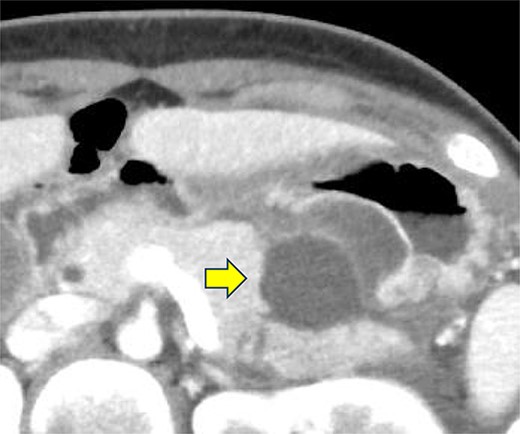

On the fifth day, the ascitic fluid increased in volume, and an open distal pancreatectomy was considered. However, her condition was stable. CT-guided abdominal drainage was performed, and a 10 Fr drainage tube was inserted for peritoneal lavage (Fig. 4). EUS-guided transgastric drainage of the pseudocyst in the omental bursa was performed. The pseudocyst was punctured; a balloon was dilated through the posterior wall of the stomach (Fig. 5a–c), and three tube stents of 7 Fr were implanted (Fig. 5d). The Amy and P-Amy levels in ascites were 9429 and 8877 IU/L, respectively; then, peritoneal lavage was performed daily. On the 12th day, contrast-enhanced CT revealed reduced pseudocyst size (Fig. 6). The patient was discharged on the 16th day (Fig. 7). Three years later, the patient is living her daily life without any complications.

CT of the pelvic region on the fourth day. An increase in ascitic fluid was observed. CT-guided abdominal drainage was performed, and a 10 Fr drainage tube was placed.